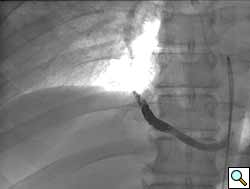

A previously healthy 43-year-old male presented with cough, fevers, and leukocytosis. A chest radiograph (Figure 1) revealed extensive consolidation in the right lower lung containing multiple cavities with air-fluid levels consistent with a necrotizing infection. A chest computed tomogram (Figure 2) showed an abscess cavity and consolidation in the right lower lobe with an aberrant blood supply from the descending aorta. This systemic blood supply was confirmed by subsequent 3D reconstruction (Figure 3). He was initially treated with IV antibiotics, resulting in normalization of his temperature and white blood cell count. He was then discharged home on a 3-week course of oral antibiotics. Three days prior to a planned surgical resection, he underwent angiographic localization of the feeding artery (Figure 4) and coil embolization (Figure 5).

To prevent complications from infection, hemorrhage, and possible malignancy, surgical resection of ILS is recommended [7]. Preoperative coil embolization of the arterial supply can decrease the risk of hemorrhagic complications and has been reported in the pediatric literature as an alternative to surgery [8]. However, intraoperative vascular control of this vessel may be more difficult if the coils are positioned in the artery outside of the sequestration rather than within the sequestration. Operative approaches involving thoracoscopy and thoracotomy have been reported, utilizing lobectomy, sequestrectomy, and wedge resection [9]. A recent review found pediatric and adult ILS anatomy, presentation, and treatment options to be similar [10].

In conclusion, we present a case of intralobar sequestration in an adult presenting with a pulmonary abscess. After a three-week course of antibiotics, preoperative coil embolization was performed to minimize the risk of intraoperative hemorrhage. An open parenchyma-sparing resection of the sequestration was performed and the patient was discharge home uneventfully after four days.